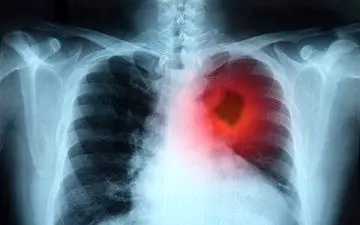

محققان انگلیسی قادر به ابداع روشی برای درمان سرطان ریه شده اند که میتواند تومورهایی که دسترسی به آنها سخت است را ظرف…